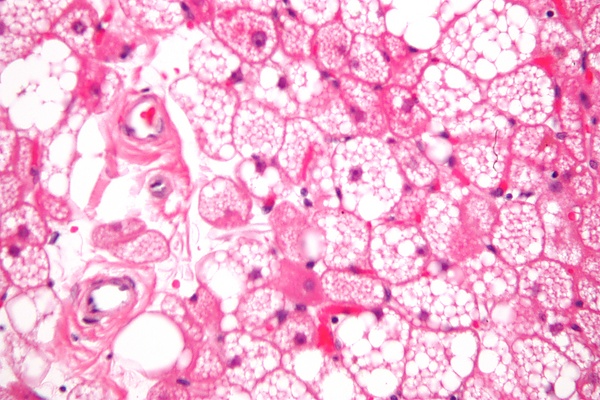

Внешне гиберномы выглядят как мягкоэластичные образования с четкими границами, имеют тонкую капсулу и дольчато снабжены выступающими сосудами. Цвет обычно коричневый или желто-коричневый — в зависимости от доли липофусцина и жировых компонентов в составе, а таже количества кровеносных сосудов. При микроскопическом исследовании гибернома состоит из бурых жировых клеток, окруженных тонкими сосудами. Бурые жировые клетки можно охарактеризовать как вакуолизированные, потому что цитоплазма клетки делится на несколько частей[1].

Гистологическая верификация является «золотым стандартом» диагностики гиберномы. При образованиях мягких тканей размером более 3 см окончательный диагноз ставится на основании морфологического заключения[1]. Возможно проведение иммуногистохимического исследования на положительную экспрессию FABP4/aP2 и S100 в клетках опухоли[7][9].